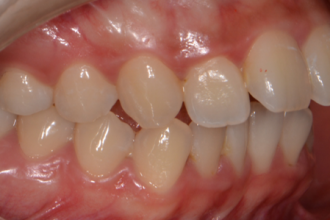

치아교정

굿프렌즈 치과 임상 케이스

직접 확인해보세요!